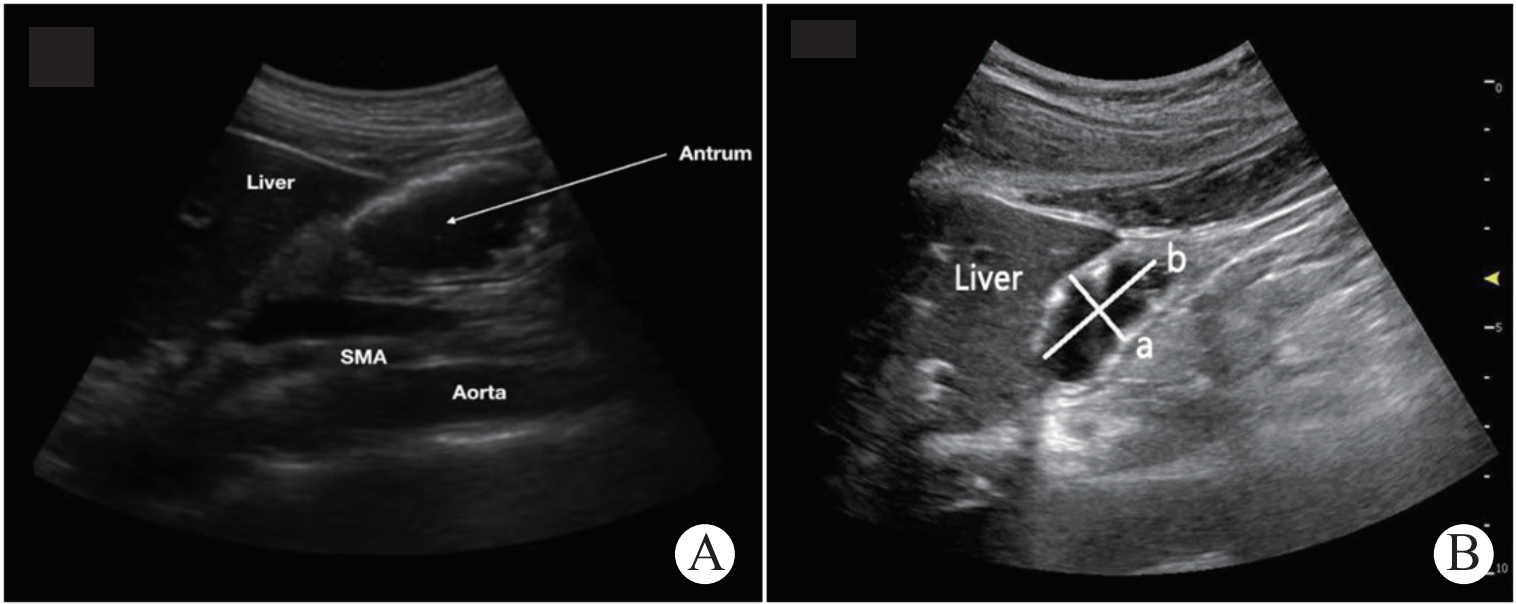

胃窦横截面积(CSA)的测量:超声治疗组患者在连续鼻饲肠内营养液后4 h监测CSA,采用非依诺M86 3~5 MHz凸阵探头进行检查,患者采取仰卧位,探头置于患者上腹部正中线稍偏右位置,寻找胃窦周围显著的解剖位置—肝左叶、肠系膜上动脉和腹主动脉,以此定位胃窦标准切面(见图 1A),旋转超声探头测量患者冠状面直径和矢状面直径进行测量。随后通过公式得出CSA值:CSA =(冠状面直径×矢状面直径× π)/ 4(π≈3.14),获得3幅静止图像,取平均值作为测量结果,GRV=27+14.6×CSA-1.28×年龄[9, 12-13]。

| 图 1 A: 胃窦部超声定位解剖标志示意图(肝脏-Liver胃窦部-Antrum肠系膜上动脉-SMA腹主动脉Aorto);B: 胃窦短轴切面超声示意图(a冠状面直径b矢状面直径) Fig 1 A: Schematic diagram of anatomical landmarks of gastric sinus ultrasound; B: Diagram of gastric sinus ultrasound short axissectional |

随着重症超声理念的不断深入,床旁超声因其安全性、无创性、简便性、可重复性、无辐射性、实时动态性等诸多优点脱颖而出。床旁超声可通过对胃窦横截面面积、胃皱襞变化、胃壁厚度、胃肠蠕动(胃肠内容物运动)等参数进行精确测量,成为监测重症患者胃肠道功能的新手段,其中又以胃窦横截面积测量评估胃排空最简便、适用,易于临床医师掌握操作[19]。其实早在1977年Bateman就首次报道了超声可探查胃充盈时的形态,1989年Marzio进一步利用流质通过胃窦切面来评估胃排空状况,也为目前的技术应用奠定了基础。之所以选择胃窦部横截面积进行测量评估,得益于胃窦的解剖位置固定、易于定位的特点,床旁超声以肝左叶、肠系膜上动脉和腹主动脉同时出现作为标准胃窦单切面(图 1A),仅需在不同体位下分别测量冠状面和矢状面直径后即可计算得出胃残余量,实时动态的监测就能够有效地有效地评估患者胃肠功能情况。尤其是中国重症超声研究组及重症血流动力学治疗协作组在2018年联合发布了关于《重症超声临床应用技术规范》,对超声探测的具体位置及操作方法进行了详细解读,更好地指导、规范了临床医生的超声应用,对于重症超声的推广具有里程碑意义。